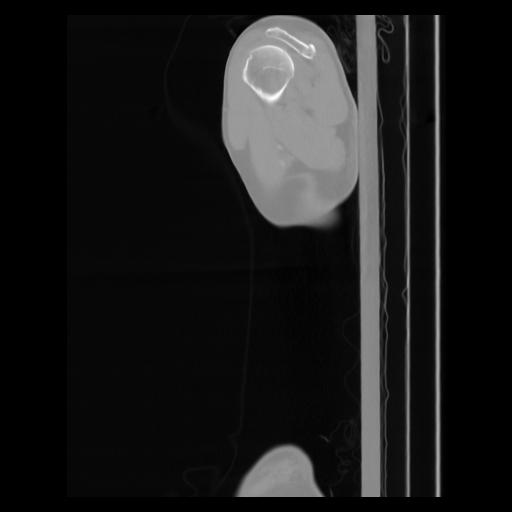

30 CUERPO,CE,Sagittal,3.000,CUERPO,Sagittal,